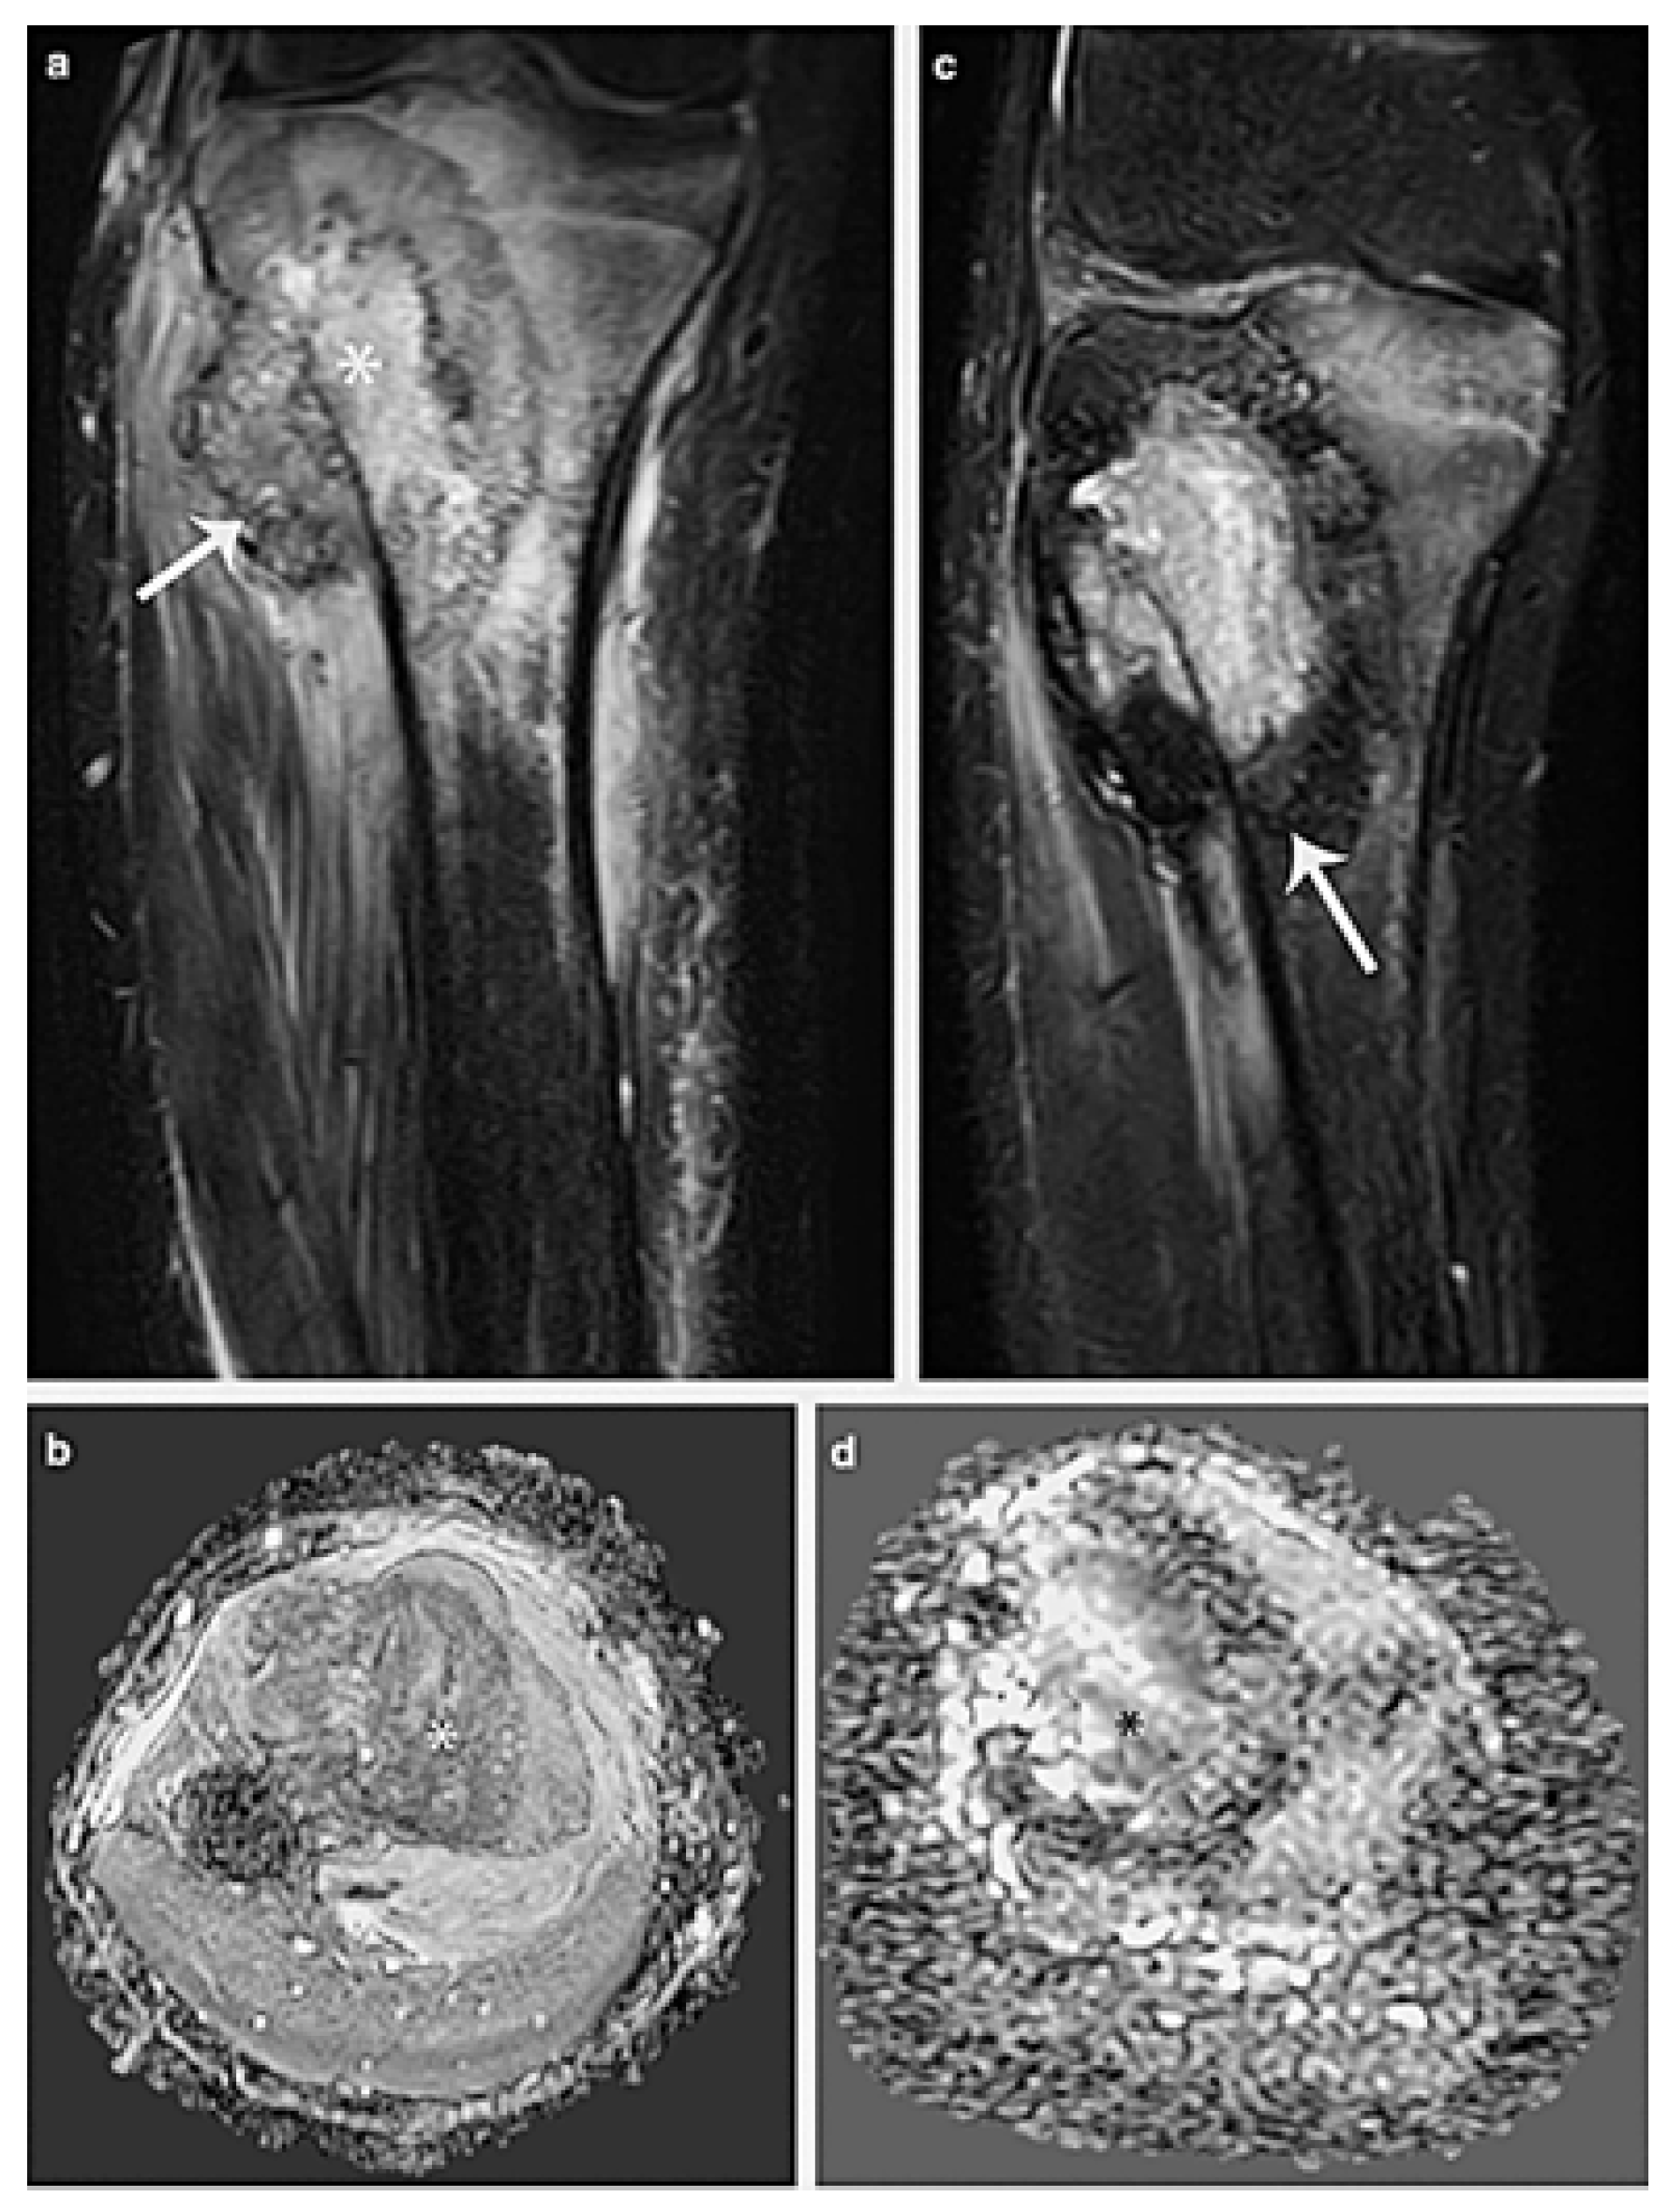

Patients with conventional osteosarcoma often undergo two courses of neoadjuvant chemotherapy before surgery [34]. A positive response to therapy is linked to a greater proportion of chemonecrosis, as observed in histopathological examinations. A good response to treatment is frequent, along with less tumour development and better clinical signs. Unlike soft-tissue tumours, osteosarcomas rarely exhibit significant shrinkage. Instead, numerous clinical studies have shown that decreased growth rates and intralesional ossification function as surrogate indicators of therapeutic response (Figure 5).

Figure 5. A 13-year-old boy has osteosarcoma affecting his proximal metaphysis of the tibia. (a) Soft-tissue mass (arrow) and a heterogeneous bone lesion (*) are seen on a coronal fat-suppressed T2-weighted MR picture. (b) The tumour’s diffusion restriction (*) is visible in the axial ADC MR picture. (c,d) MRI after chemotherapy. (c) A peripheral hypointense rim in the tumour that suggests calcification can be seen on the coronal fat-suppressed T2-weighted MR image (arrow). (d) When compared to the original research, the axial ADC MR image demonstrates a reduction in the diffusion restriction areas (*), suggesting a positive response to treatment. Narejos Clemente et al. [35].